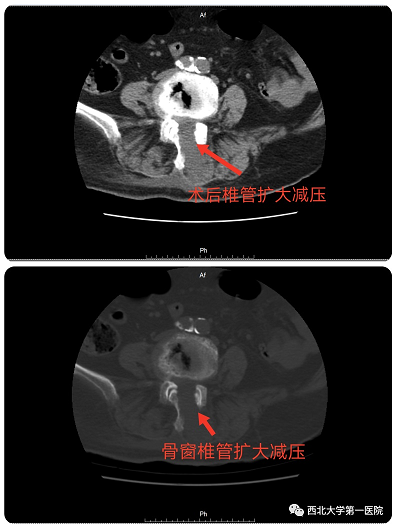

术后复查CT可见椎管彻底减压

经过充分的术前讨论及围手术期多学科讨论评估后,决定采用目前最新脊柱内镜技术:OSE(Open Spine Endoscope)单孔脊柱内镜技术,行腰4-5椎管狭窄单侧入路、双侧减压、脊神经根粘连松解术。手术切口约2cm,术中出血10ml左右,由于不破坏关节突关节,不影响脊柱稳定性。术后第二天患者佩戴腰带下地活动,症状明显缓解,效果非常满意。

术中可见椎管减压彻底,神经根完全松解